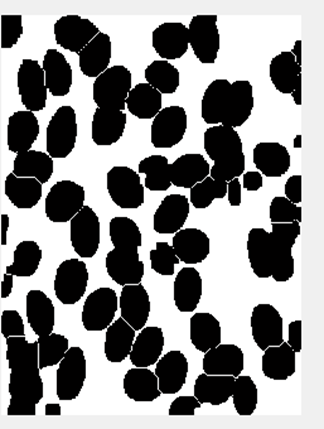

本文基于Matlab设计显微镜下血液细胞图像分割与计数系统,可以分割血液细胞图像中的多个细胞,并对分割后的细胞计数,能处理多个细胞部分重叠以及细胞位于图像边缘的特殊情况。设计步骤主要包含细胞图像预处理、图像预分割、重叠细胞分割、细胞计数等。准确的分割细胞,对于后续细胞分析很重要。分割的质量将会影响细胞图像的分析、识别与研究的正确性。因此,在医学领域,细胞分割和统计功能很重要,细胞自动识别和分析的关键困难就在于此。通过比较各种图像分割算法的优劣性,最终采用了阈值二值化分割方法分割细胞,运用分水岭算法对粘连细胞进行分开处理,每个细胞都相当于一个连通域,经过计算连通域的数目,即可得到图像中细胞的个数。

本设计能通过对显微镜下血液细胞的彩色图像进行处理和分析,统计出图像中的细胞个数,对于重叠的细胞能进行分割,位于图像边缘的细胞也能识别出来,准确率达到95%以上,与手工统计的方法比较,该方法对工作效率有显著的增加。

3.3 重叠细胞分割 11

4.2 重叠细胞分割与细胞计数程序设计 16

4.2.1 重叠细胞分割程序实现 16